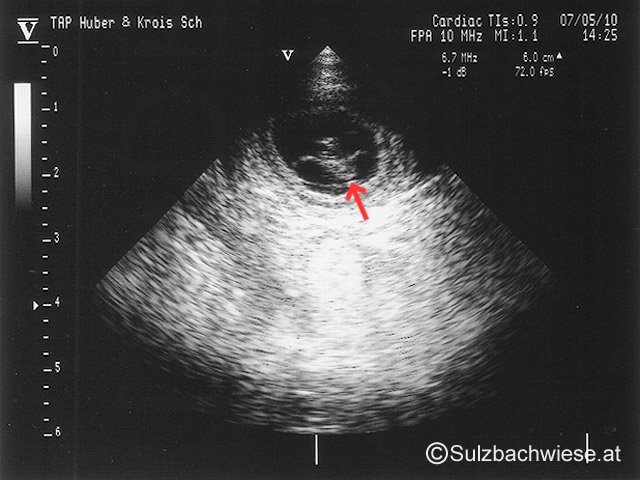

Yoker Leithawald & Akira Sulzbachwiese

Wurfdatum: 14.06.2010